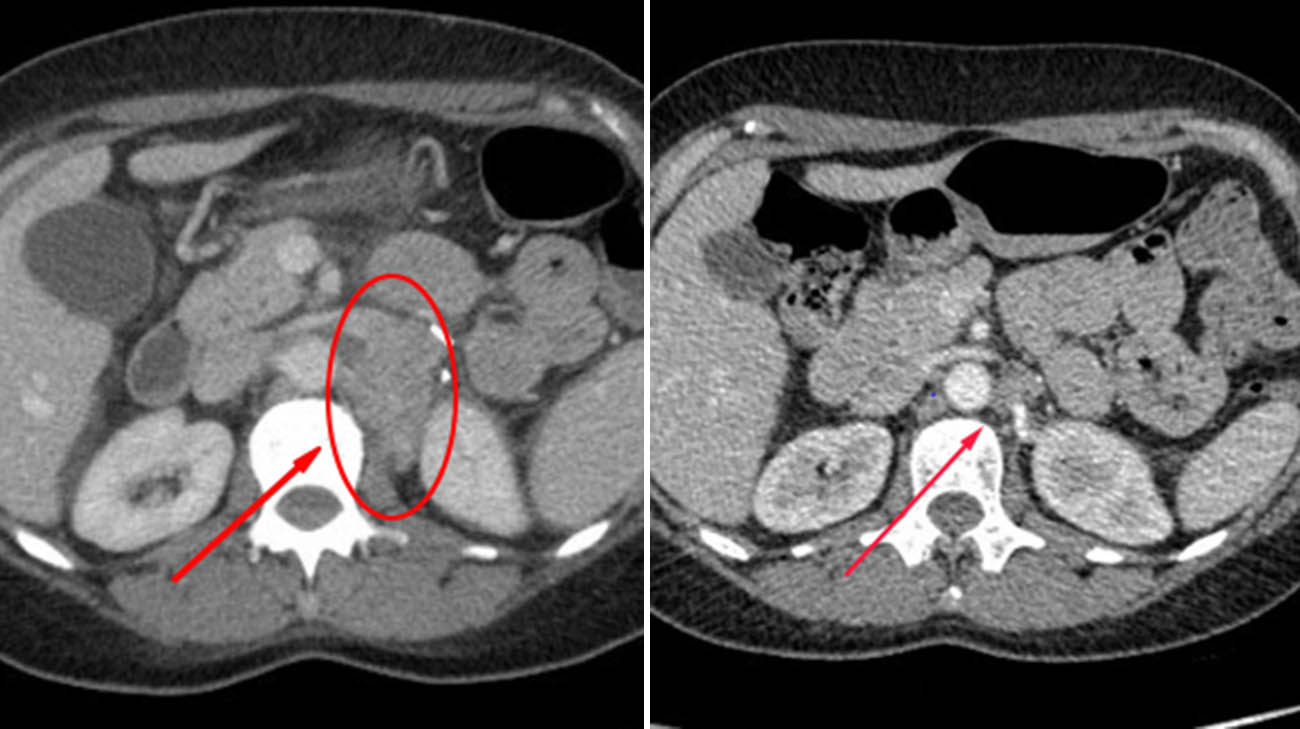

CT scans of Missy's cancer before receiving TIL (left) and 12 weeks after TIL (right). (Courtesy: Cleveland Clinic)

After undergoing TIL therapy, Missy returned to her favorite pastimes, like running, and is enjoying spending time with her husband and two children in between work. Imaging less than six months after treatment showed promising results, with the tumors starting to shrink.